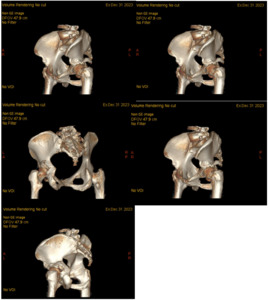

A 64-year-old female with diabetes, hypertension, and dyslipidemia was involved in a motor vehicle accident, resulting in significant injuries. She presented to the Emergency Department via Medivac and underwent a comprehensive trauma assessment. Orthopedic evaluations reveal a fractures dislocation of the left acetabulum with a posterior wall fracture and a femoral head fracture (Figure 1. Figure 2, Figure 3). Additionally, a minimally displaced fractures of the left tibial plafond was identified. Due to the complexity of her injuries and considering her age, a surgical plan was formulated for fixations of the acetabular and femoral head fractures, along with total hip replacements on the left side, and fixations of the tibial plafond fractures. After induction of general anesthesia and regional block, the patient was positioned in lateral decubitus for the hip procedures. Utilizing the Kocher-Langenbeck approach, the posterior wall fracture was stabilized with lag screws and a buttress plate (Figure 4A, 4B). The hip was then dislocated, the femoral neck cut, and the acetabulum reamed. A Stryker Trident cup size 46 was inserted for a press-fit, augmented with three screws, and a metal liner for dual mobility was added. Subsequently, the femur was broached, and an Accolade stem size 2 with a double head was implanted, ensuring excellent stability and appropriate legs length (Figure 4C). The operation concluded with thorough irrigation and closure in layers. The patient was then repositioned supine to address the tibial plafond fracture, which was stabilized with a single medial plate, followed by application of a dry dressing and a below-knee backslabs. Postoperatively, the patient experienced mild pain but was otherwise stable. Dressings on the left hip and ankle were intact, with ankle motion preserved and a palpable dorsalis pedis pulse. She began mobilization with physiotherapy from day one and showed no active complaints throughout her recovery, proceeding smoothly until discharge (Figure 5).